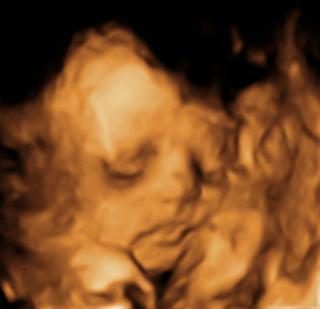

@buburka ano,bola som na tom farebnom 4D, asi pol hodinu,platili sme 67 eciek a boli sme tam cela rodinka, len malinka nechcela spolupracovat,stale sa zakryvala ruckami,potom nozkami a nakoniec zavadzal pupocnik,tak som sa sla prejst po schodoch,nakoniec sa nam podarilo nejake fotky a videa napalit,dostali sme CD asi 20 fotiek a 6 videii, mame pamiatku,dostali sme aj prenatalny reklamny kufrik,urcite to je zazitok,my sme este nevedeli pohlavie takze nam ukazali malu buchticku a vieme ze je v poriadku, uz otocena dole hlavickou. U svojho lekara by som zaplatila 22 tak si mozes porovnat ten rozdiel, prikladam foto 🙂